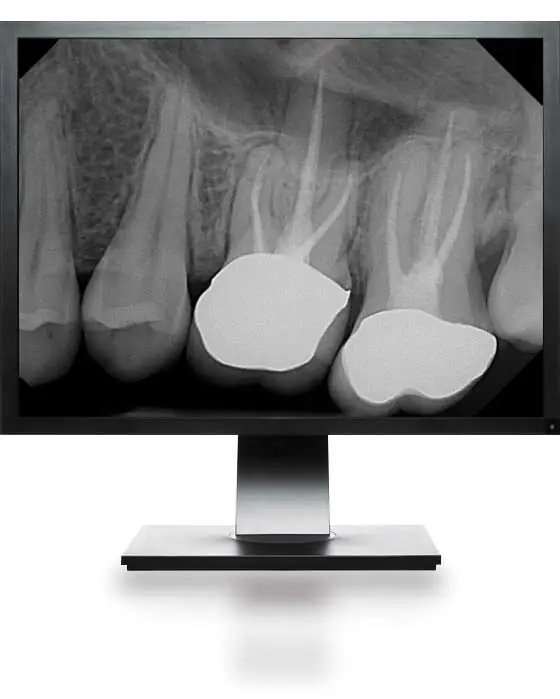

DentiMax Dream Dental Sensors provide crystal-clear digital images. It represents the latest in CMOS technology with an active pixel chip. The dental digital radiography includes an industry-leading and highly sensitive scintillator with a fiber optic plate. DentiMax houses them in a module that includes a built-in circuit board on the chip.

The image quality by design works better than film because it allows dental offices to zoom, spotlight, and enhance areas from suspected caries. Additionally, it also addresses any concerns directly on a computer screen.

Updated dental image filters and processing algorithms improve overall image quality. New calibration files completely remove "fixed pattern noise." It creates much cleaner dental x-ray sensors.

Diagnostic tools help clinical digital x-ray evaluations by providing better patient education and dental treatment plans.